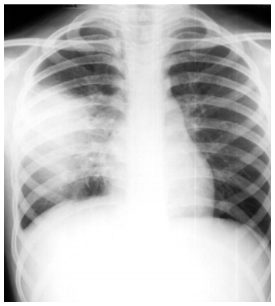

Paciente de 37 anos de idade, procura

UPA referindo apresentar há dois dias mal

estar geral, dor torácica ventilatório

dependente à D e tosse produtiva, com

expectoração amarelada e febre aferida

38ºC. É hipertenso, em uso de losartan. Ao

exame físico apresenta-se lúcido, orientado,

pouco dispneico, com mucosas

normocoradas, hidratadas, escleróticas

anictéricas; ao exame pulmonar apresenta

aumento do frêmito toracovocal em terço

médio de hemitórax D, onde ausculta-se um

sopro tubário; ritmo cardíaco regular em

dois tempos com bulhas normofonéticas, sem sopros. Abdome flácido, ausência de

visceromegalias. Membros inferiores sem

alterações. Sinais vitais: PA = 140/80

mmHg, FR = 24 irpm, FC = 92 bpm e

temperatura axilar = 37,8ºC. Foi realizado

RX de tórax no atendimento, o qual é

mostrado abaixo. Assinale a alternativa que

corresponde CORRETAMENTE ao

ambiente para o tratamento inicial e o

antibiótico de escolha.